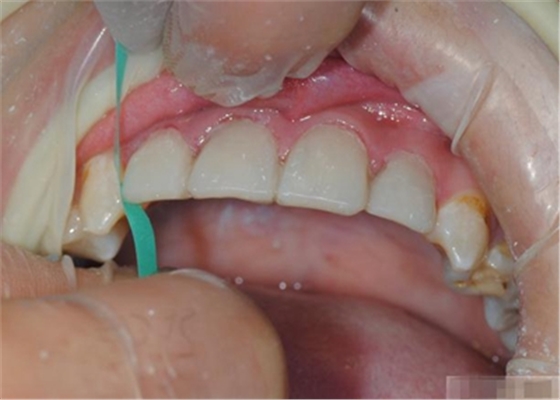

制作舌側(cè)背板

使用事先制作完成的硅橡膠模板。它是由技師在做好的美學(xué)蠟型的模型上制作的。這樣的方法為牙醫(yī)提供了許多便利:

c,硅膠模板使牙體修復(fù)簡(jiǎn)化,可以首先堆塑牙體的舌側(cè)面,這也是Dr.Vanini分層堆塑技術(shù)的基礎(chǔ),使用硅膠制作的膠刷會(huì)使堆塑更加簡(jiǎn)單;